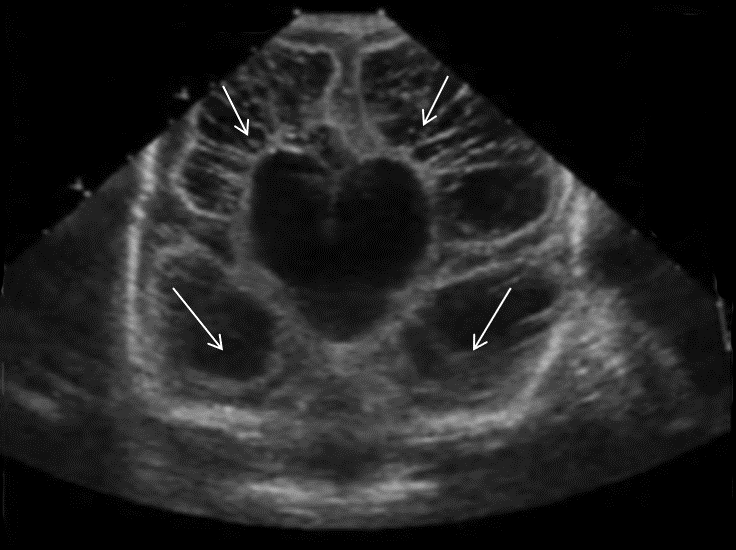

Neonatology Grade 4 PVL 2 Image